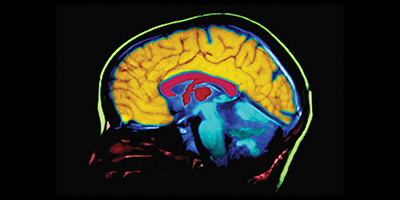

• Pruebas (como análisis de sangre y estudios de imágenes cerebrales) para descartar otras causas de síntomas similares a los de la demencia.

Conozca los efectos de la enfermedad de Alzheimer sobre el cerebro.